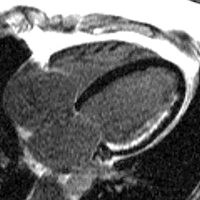

The search for a cure is happening now. When you have a heart attack, a portion of your heart muscle is damaged and dies. At the moment, once your heart is damaged, you will live with that damage for the rest of your life – it cannot be reversed.

The British Heart Foundation is the biggest independent funder of heart research in the UK. Now because of recent advances in regenerative medicine, there is real hope for a cure. Every day our scientists are getting closer to understanding how to repair the damage caused by heart attack and they have already made some astonishing breakthroughs.

Our researchers can already make heart cells in the lab using stem cells. Stem cells have the potential to lead to a new treatment for heart failure.

The Golden Jubilee National Hospital, home to the Scottish National Advanced Heart Failure Service (SNAHFS), will participate in one of two trials announced by the British Heart Foundation. Along with the Royal Brompton Hospital, the UK recruitment centres for this multi-centre, international trial, aim to recruit 200 patients who have severe chronic heart failure and are currently on ‘optimal’ treatment.